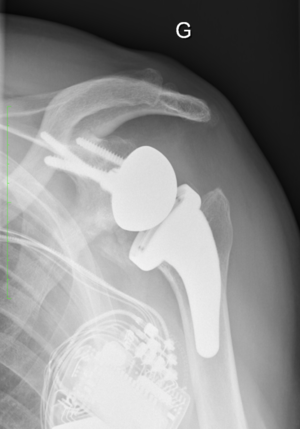

Glenohumeral Osteoarthritis With Severe Glenoid Bone Loss

The use of reverse shoulder arthroplasty in patients with severe glenoid bone loss and osteoarthritis is the best option. Excellent results have been reported in patients with osteoarthritis, an intact rotator cuff and substantial glenoid bone loss treated with reverse shoulder arthroplasty with or without bone grafting (Video).

Fifty-one years old patient with right glenoid dysplasia (C glenoid) and an intact rotator cuff. Computed tomography (CT) scan of the shoulder shows 60 degrees of retroversion. The patient has been treated with combined bony and metallic augmentation. At three months follow-up, range of motion improves and imaging reveals satisfactory glenoid reconstruction.